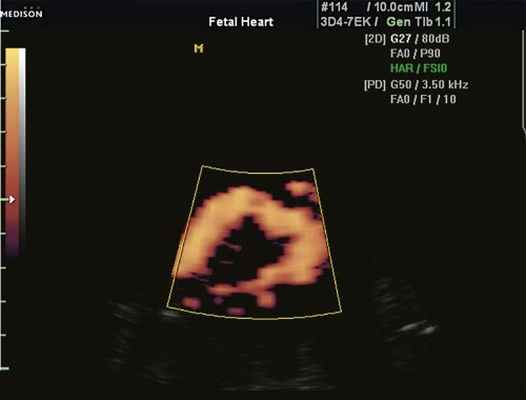

Существует еще и понятие как псевдокоарктация, или "кинкинг" аорты - деформация аорты, аналогичная классической коарктации, но препятствие кровотоку незначительное, так как имеется простое удлинение и извилистость аорты (рис. 5).

Рис. 5. Кинкинг аорты у плода в 34 нед беременности. Исследование в энергетическом режиме.